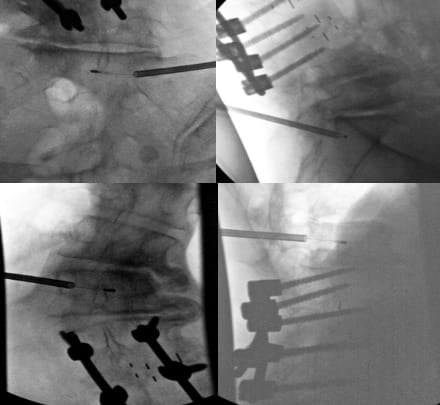

Monitored anesthetic care is the most common type of anesthesia performed, although general anesthesia is an option as well. Local anesthesia is administered, followed by careful trocar advancement under fluoroscopic guidance. It is very important to check AP and lateral images to ensure that the trocar does not violate the medial border of the pedicle on the AP image prior to breaching the posterior wall of the vertebral body on lateral imaging. The trocar passes through the lateral pedicle aspect, staying superior to inferior cortex and lateral to medial cortex. Once the posterior vertebral body cortex is breached, the curved cannula assembly is advanced toward the stem of the basivertebral nerve at a point located 30%-50% of the sagittal diameter of the vertebral body (closer to the posterior wall). This allows for radiofrequency probe positioning proximal to the location of basivertebral nerve arborization. Final probe positioning varies by vertebral level to optimize targeting of the basivertebral nerve terminus. For the L3, L4, and L5 levels, the probe should be positioned at the midpoint between the superior and inferior endplates (approximately 50% of the cephalo-caudal diameter of the vertebral body) and 30-50% of the vertebral body width from the posterior wall (Figure 2). However, S1 vertebral anatomy requires modified positioning due to the unique sacral morphology. At the S1 vertebral body, the probe should be positioned closer to 50% of the sagittal diameter from the posterior wall and approximately 40% of the distance from the superior endplate to the inferior endplate. Proper positioning at each level is confirmed through multiple fluoroscopic views in both AP and lateral projections before initiating the ablation cycle.

While FDA approval covers the L3-S1 levels, select cases may warrant treatment of higher levels with modic changes and a high level of confidence that the motion segment is a source of pain. Treatment above L3 requires exceptional care due to the progressively smaller pedicles and proximity of the neural structures (Figures 3 and 4).

Critical considerations include (1) mandatory pedicle diameter measurement, (2) CT scan for pre-procedure planning is strongly recommended, (3) modified trajectory angles (ie parapedicular or extrapedicular approaches) to accommodate anatomy, (4) increased vigilance for neural structure proximity, and (5) potential for vascular trespass if an extrapedicular approach is being considered (segmental arteries).